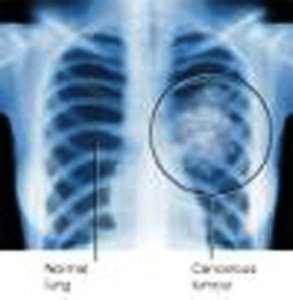

Applicato alle immagini digitali ottenute con una tomografia computerizzata, lo strumento, potrebbe essere utilizzato come supporto per lo screening dei tumori polmonari, ancora oggi una delle più letali forme di neoplasia.

Lo strumento, chiamato M5L, è un software basato su questa premessa: la ricerca dei noduli polmonari nelle tomografie del torace è un compito complesso che necessita di lunghi tempi di analisi. Si tratta in genere di esaminare centinaia di “fette” del corpo acquisite dalla tomografia, in cui sono presenti strutture complesse (vasi e bronchi) che rendono difficoltosa l’individuazione dei noduli. Serve quindi un software in grado di identificare le strutture presenti nel volume polmonare, distinguendo in particolare i noduli da vasi e bronchi e segnalandoli al medico.